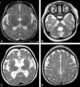

Cockayne syndrome (CS), also called Neill-Dingwall syndrome, is a rare and fatal autosomal recessive neurodegenerative disorder characterized by growth failure, impaired development of the nervous system, abnormal sensitivity to sunlight (photosensitivity), eye disorders and premature aging. Failure to thrive and neurological disorders are criteria for diagnosis, while photosensitivity, hearing loss, eye abnormalities, and cavities are other very common features. [Source: Wikipedia ]

Intracranial calcification

Leukodystrophy / leukoencephalopathy

Microcephaly

Multiple intracranial calcification